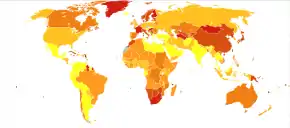

Epidemiology

In 2017, the Global Burden of Disease Study estimated there were 1.1 million new cases;[17] in 2022 the World Health Organization (WHO) reported a total of 24 million cases globally.[2] Schizophrenia affects around 0.3–0.7% of people at some point in their life.[16][11] In areas of conflict this figure can rise to between 4.0 and 6.5%.[242] It occurs 1.4 times more frequently in males than females and typically appears earlier in men.[83]

Worldwide, schizophrenia is the most common psychotic disorder.[52] The frequency of schizophrenia varies across the world,[7] within countries,[243] and at the local and neighborhood level;[244] this variation in prevalence between studies over time, across geographical locations, and by gender is as high as fivefold.[5]

In 2000, WHO found the percentage of people affected and the number of new cases that develop each year is roughly similar around the world, with age-standardized prevalence per 100,000 ranging from 343 in Africa to 544 in Japan and Oceania for men, and from 378 in Africa to 527 in Southeastern Europe for women.[245]